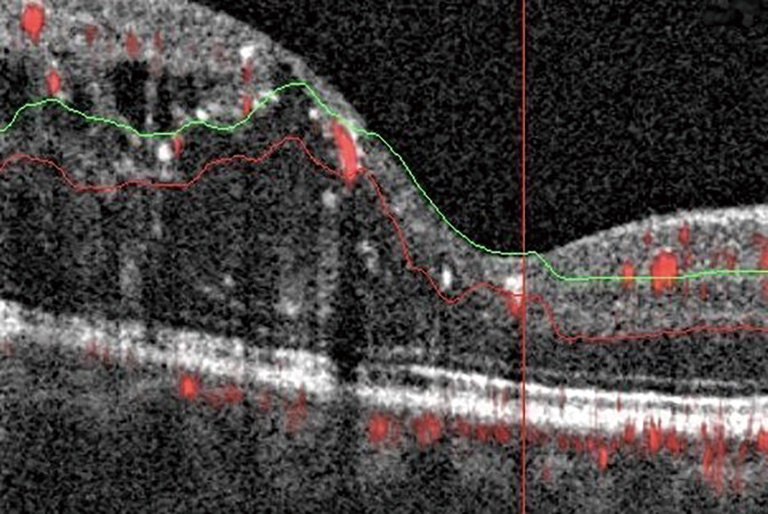

Analyzing Relative Flow Speeds In Diabetic Retinopathy Using Variable Interscan Time Analysis Oct Angiography Ophthalmology Retina

Pdf A Review Of Optical Coherence Tomography Angiography Octa

A Review Of Optical Coherence Tomography Angiography Octa Springerlink